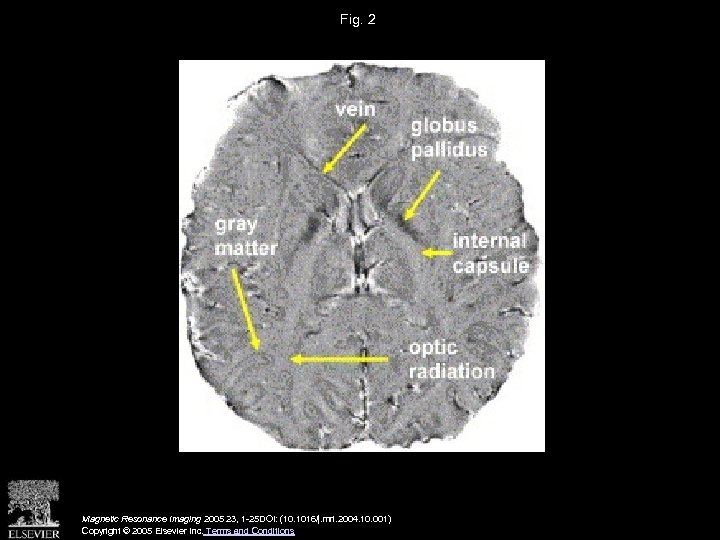

Fig. 2 Magnetic Resonance Imaging 2005 23, 1 -25 DOI: (10. 1016/j. mri. 2004. 10. 001) Copyright © 2005 Elsevier Inc. Terms and Conditions